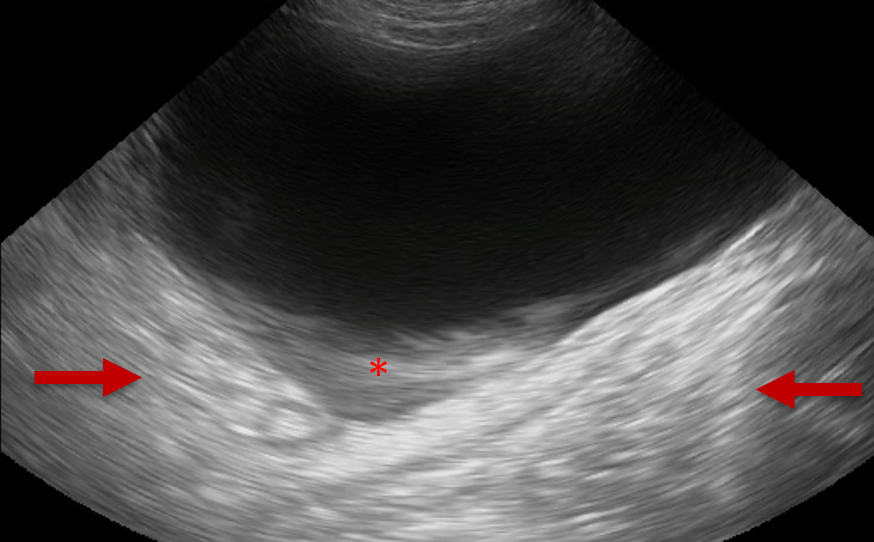

Several ultrasonographic artefacts can present whilst imaging the bladder and these can be detrimental to obtaining diagnostic images. Side lobe artefact and slice thickness artefact can both mimic the appearance of abnormal structures within the bladder lumen (Figure 3).

Figure 3. Slice Thickness Artefact – In this sagittal plane image of the bladder, slice thickness artefact has caused the appearance of material within the bladder lumen (*). The anechoic fluid filled bladder is also causing distal acoustic enhancement. This causes the tissues distal to the bladder to appear relatively hyperechoic (between arrows).

Orientating the transducer to ensure that the ultrasound beam is perpendicular to the bladder wall in the region of interest will aid differentiation between an artefact and true thickening or mass lesions associated with the wall.4

Because the fluid content of the bladder is minimally attenuating to ultrasound, the tissue deep to the bladder will appear hyperechoic as a result of the ultrasound waves arriving to that area with more energy. This is known as distal acoustic enhancement (Figure 3). Reducing the far field gain can help to differentiate normal from abnormal.